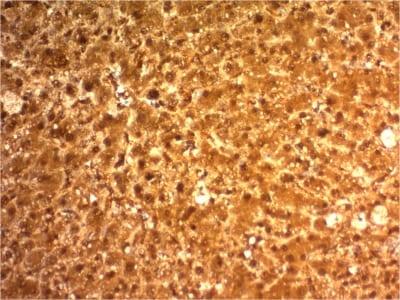

293Tcells. Hepatocellular Carcinoma (HCC).

IHC, FFPE (verified)

IHC (FFPE) (verified)

Higher concentration may be required for direct detection using primary antibody conjugates than for indirect detection with secondary antibody|Immunohistology (formalin): 2-4 ug/mL for 30 minutes at RT|Staining of formalin-fixed tissues requires boiling tissue sections in 10 mM citrate buffer, pH 6.0, for 10-20 minutes followed by cooling at RT for 20 minutes|Optimal dilution for a specific application should be determined by user